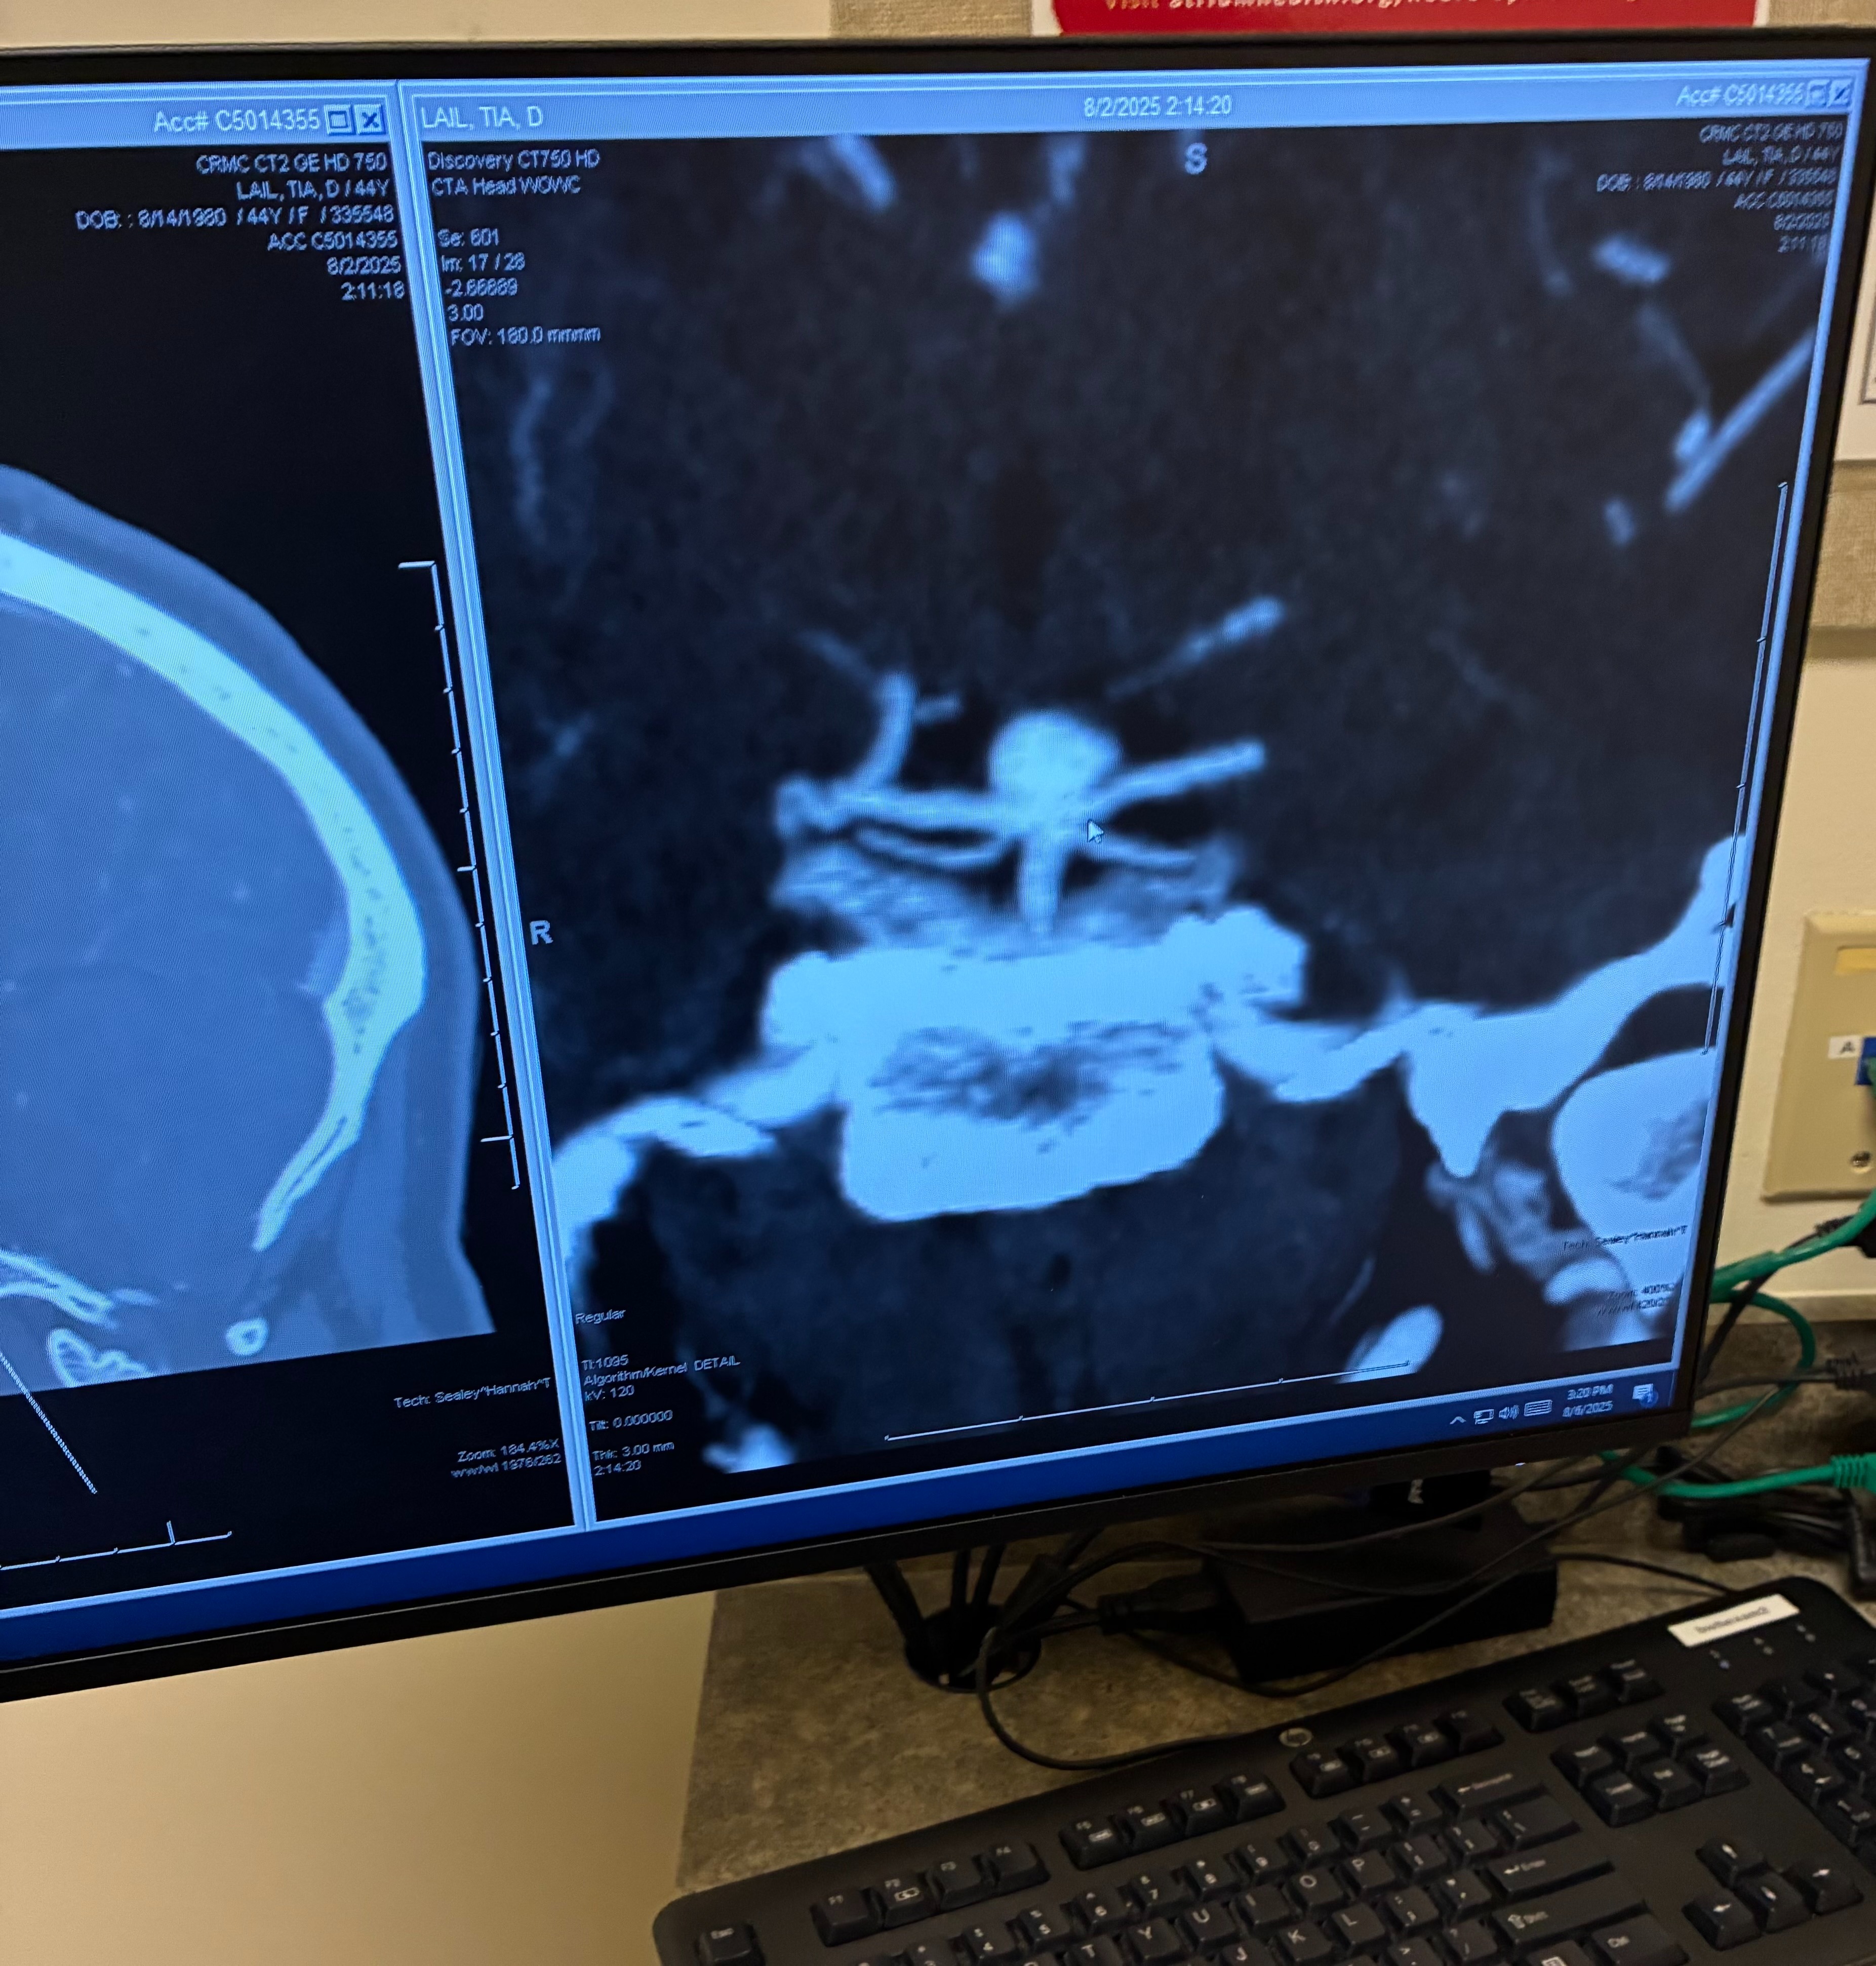

⚠️ A Life-Threatening Discovery We rushed her to the ER and trauma center. After several tests, doctors made an incidental discovery that may have saved her life: An 8mm Basilar Artery Aneurysm—a rare and potentially fatal condition. “The aneurysm is located at the base of her brain in an artery that feeds both sides. If it ruptures, it will likely be fatal.” My wife is the rock of our home.